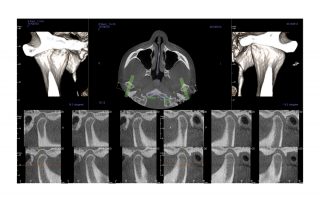

This dynamic system offers three maximum fields of view (FOV), V8, V10, and V17. Within these sizes, you also have the option to scale or collimate the scan height to capture only the area of interest per the patient’s immediate need. The system also provides enhanced low-dose imaging options through protocols and collimation, dedicated traditional 2D panoramic capabilities, and the feature-rich Tx STUDIO™ software.

The V8 represents your gateway into the world of industry-leading 3D CBCT imaging at an affordable price. With 8cm x 5cm and 8cm x 8cm FOVs, this system accommodates those clinicians who want to capture select treatment areas for survey – implant, oral surgery and endodontic.

The i-CAT FLX V10 combines highly precise cone beam 3D technology with flexible planning and treatment tools. The i-CAT offers a full suite of solutions to meet the needs of your practice. V10 scan sizes range from an adjustable 8cm x 5cm to 16cm x 10cm.